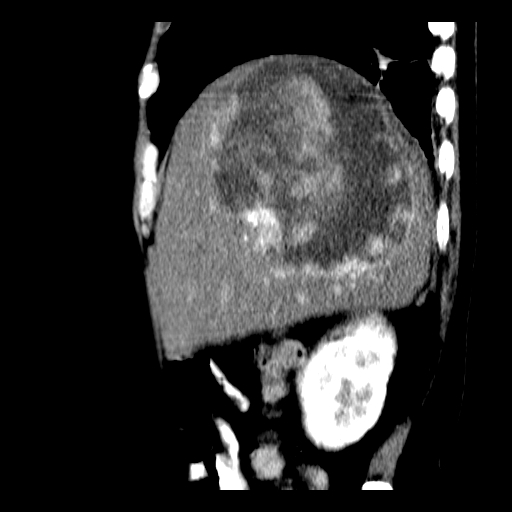

以下是引用卜一在2008-6-23 15:38:00的发言:[br]本例延时期的图象未扫完,单纯平扫 动脉期及门脉期特征分析:平扫低密度较大肿块,内见不规则出血灶,界限清楚。动脉期边缘结节样强化,门脉期病灶边缘进一步强化并范围明显缩小。因此考虑:血管瘤伴出血!

以下是引用深泽交通医院在2008-6-23 16:40:00的发言:[br]考虑肝癌伴出血.诊断依据:平扫瘤壁结节密度低于肝实质,动脉期壁结节明显强化,门脉期略低于肝实质密度[br]病灶有明显的假包膜,